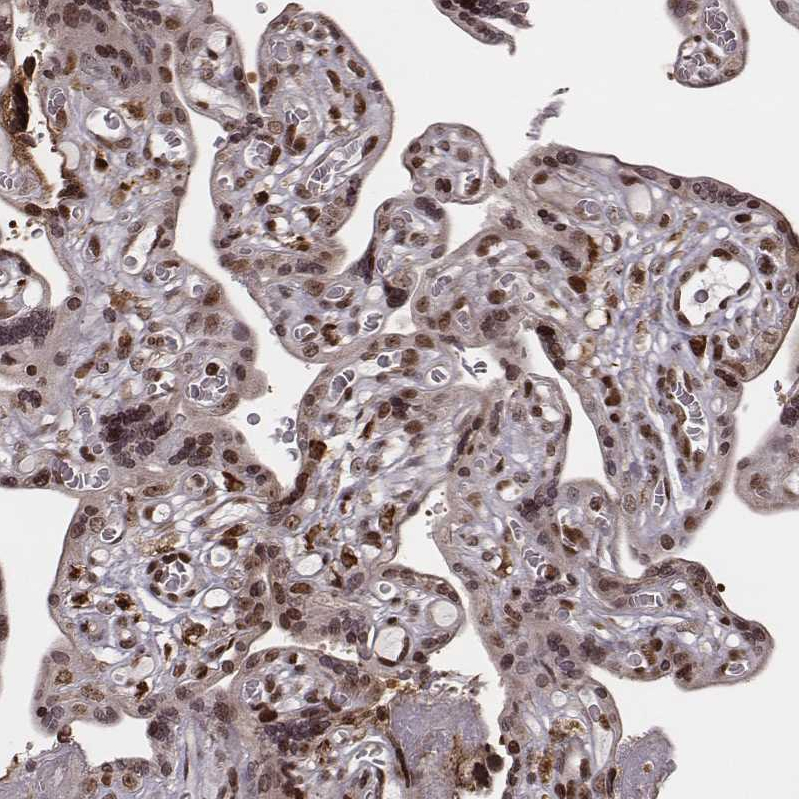

Immunohistochemical staining of human testis shows strong nuclear positivity in cells in seminiferous ducts.